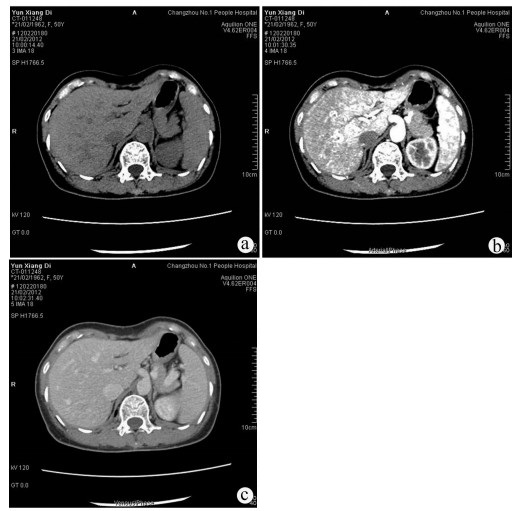

经皮冷冻消融联合无水酒精注射治疗70岁以上老年肝细胞癌患者的效果及安全性分析

罗婧, 吕采红, 杨永平

2022, 38(2): 365-371. DOI: 10.3969/j.issn.1001-5256.2022.02.021

摘要(972) HTML (364) PDF (2738KB)(63)

摘要:

目的  探讨经皮冷冻消融(CRYO)联合无水酒精注射(PEI)对早期老年肝细胞癌患者的疗效和安全性。  方法  回顾性纳入解放军总医院第五医学中心2014年1月—2018年1月收治的92例老年肝细胞癌患者,其中单一CRYO治疗组46例,CRYO联合PEI(联合治疗)组46例。比较两种治疗方式的效果,不良反应及治疗前后肝功能相关指标的变化,并随访患者肿瘤的复发及生存预后情况。正态分布的计量资料两组间比较用t检验;非正态分布的计量资料两组间比较采用Mann-Whitney U秩和检验。计数资料两组间比较采用χ2检验。两组的生存时间采用Kaplan-Meier方法进行生存分析,并用log-rank检验生存曲线的差异;通过Cox回归法确定影响生存预后的独立危险因素。  结果  联合治疗组和CRYO组初次消融的有效率分别为89.1%和73.9%,组间差异无统计学意义(P>0.05)。CRYO组和联合治疗组患者术后总生存率和无瘤生存率间的差异均无统计学意义(P值均>0.05),但联合治疗组患者术后第1、2和3年局部肿瘤进展率分别为20%、21%和21%,明显低于CRYO组的30%、46%、46%(χ2=4.187,P<0.05)。多因素Cox回归分析提示行单一CRYO治疗可能是局部肿瘤进展率的独立危险因素(HR=2.206,95%CI: 1.003~4.850, P=0.049)。在不良反应的发生率上两组间差异没有统计学意义(P>0.05),但CRYO组有3例严重不良反应,联合治疗组未出现严重不良反应。  结论  对于早期老年肝细胞癌患者,CRYO联合PEI治疗较单纯CRYO治疗安全有效,能明显降低局部肿瘤进展率。